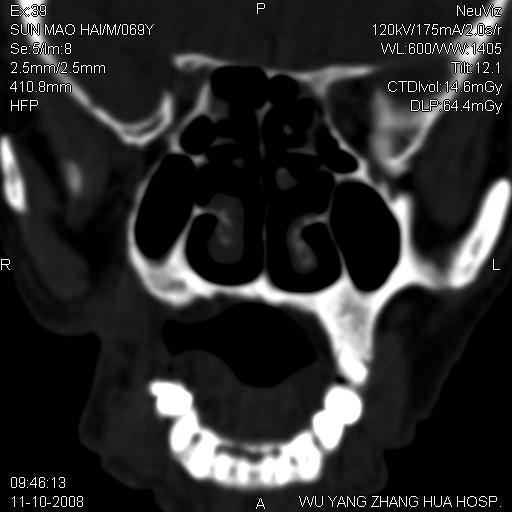

标题: CT16568:右面部瘘管半年余,无其它不适. [打印本页]

标题: CT16568:右面部瘘管半年余,无其它不适.

考虑右上颌异位齿(或斜向阻生齿)并根尖脓肿。

1.右上颌异位齿

2.右上颌化脓性骨髓炎

3.右下鼻甲肥大